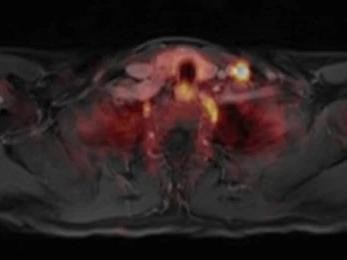

Ein 66-jähriger, asymptomatischer Patient wird aufgrund eines ansteigenden PSA-Werts zur multiparametrischen Magnetresonanztomographie (mpMRT) der Prostata überwiesen. Die digital-rektale Untersuchung war unauffällig. Die initiale mpMRT zeigt keine karzinomsuspekten Veränderungen. Aber die Kontrastmittelkinetik ist auffällig.

Einem Mann wird Blut abgenommen/© auremar / stock.adobe.com (Symbolbild mit Fotomodellen), Jüngere Hand hält ältere Hand/© Joel bubble ben / stock.adobe.com (Symbolbild mit Fotomodellen), Radionuklidtherapie bei einem Patienten mit metastasierten kastrationsresistenten Prostatakarzinom /© Willner L et al. / all rights reserved Springer Medizin Verlag GmbH, Koloskopie/© Kzenon / stock.adobe.com (Symbolbild mit Fotomodellen), Infusionstropf im Krankenhaus /© Trsakaoe / stock.adobe.com, Blut wird abgenommen/© geargodz / stock.adobe.com (Symbolbild mit Fotomodellen), Ga-PSMA-PET MRT Verdacht auf Prostatakarzinom/© Springer Medizin Verlag GmbH, Typisches Beispiel eines intraduktalen Karzinoms der Prostata./© Kristiansen, G. et al. / all rights reserved Springer Medizin Verlag GmbH, Mann nimmt eine Tablette ein/© Jelena Stanojkovic / stock.adobe.com (Symbolbild mit Fotomodell), Blutproben im Labor/© PeopleImages / Getty Images / iStock, Urologe erklärt Patienten urologischen Eingriff an einem Modell /© Witoon / Stock.adobe.com (Symbolbild mit Fotomodell), Muzinöses Prostatakarzinom/© Garzaro JRR et al. / all rights reserved Springer Medizin Verlag GmbH, Hypertrophe, teils pseudopolypös anmutende Schleimhautfalten, mit Koagel, Sickerblutung und Hämatin/© H. Lutz, PSMA-spezifische Traceranreicherung zweier Lymphknoten tief linkszervikal/© Lingl, J.P., Böhm, F., Wiegel, T. et al., Ein Mann erhält eine Infusion/© Denis / Stock.adobe.com (Symbolbild mit Fotomodell), Search Icon, Teaserbild Blutungsrisko managen bei Antikoagulation - Waage/© Leo Pharma GmbH, Vortrag Frankfurter Gerinnungssymposium/© LEO Pharma GmbH (Screenshot aus Vortrag), 3 Empfehlungen für niereninsuffiziente Patienten/© LEO Pharma GmbH, Thrombus und Patientin im Gespräch/© crevis / adobe.stock.com (Symbolbild mit Fotomodell)